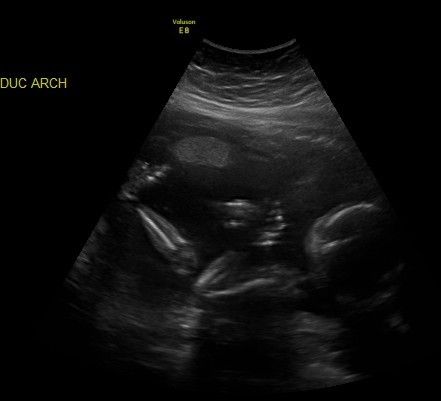

But of all God's miracles in our world, none is more special than this ultra sound of Kendra, taken shortly after we learned that she would be born with Spina Bifida, but before we had any clue how severely she might be affected. I'm gonna post the picture, and you tell me what you see. Right after Jen gave me my ultrasound printout I spotted this, and I relaxed. I knew Kendra was going

to be just fine, and that her future was in greater hands than ours. If you see it, let me know. If you have trouble I'll point it out. Ready, set, GO!!

Sounds like a very wise, very loving preacher! Okay, I'm gonna post another picture - same one - with the surprise pointed out

Do you see Kendra's Guardian Angel right there with her? You may have to lean back a little, but she's there!

Look right at the intersection of the four lines.....and just a little below to the right. There's a face, and you can see her hairline almost on the line. She's right below the word "Angel".